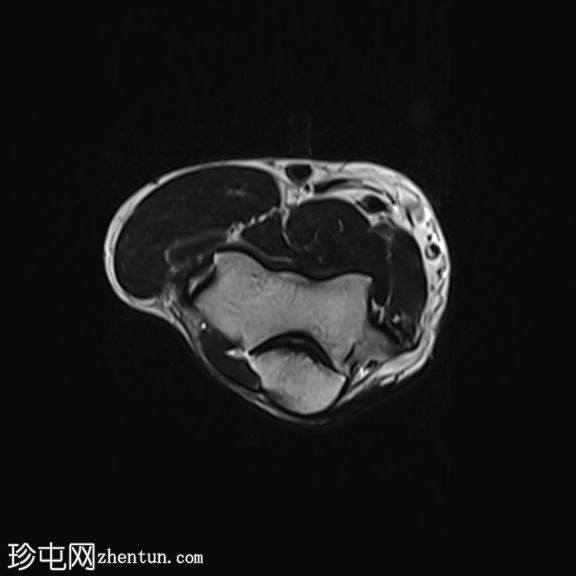

轴位

T2加权像

STIR序列

肘关节伸肌总腱增厚,腱内可见高信号及部分撕裂。伴周围软组织水肿。